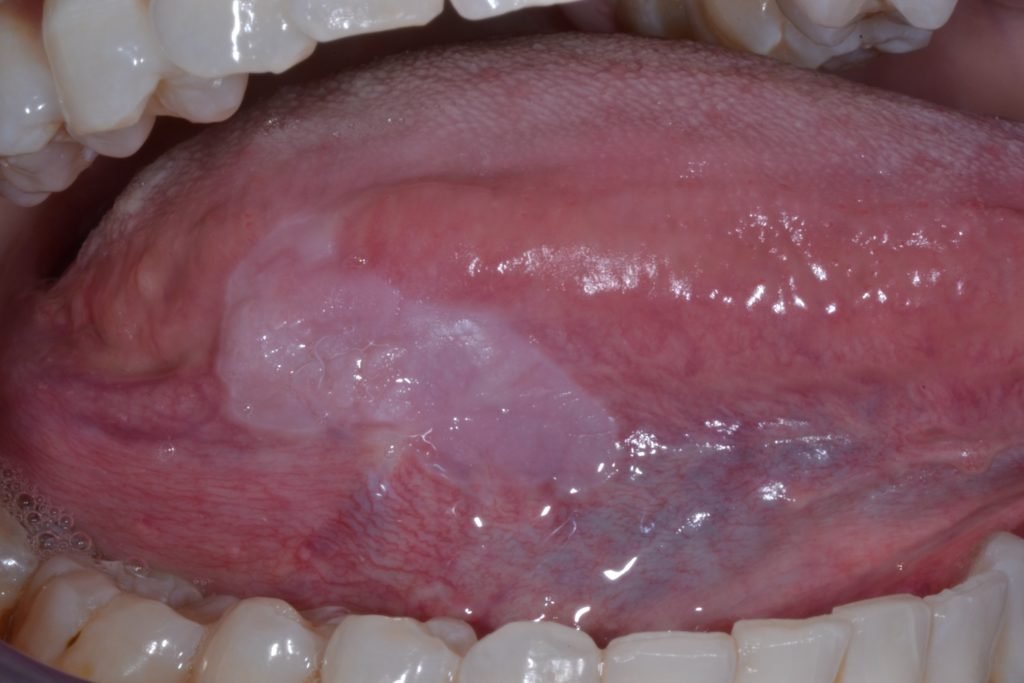

Leucoplasie Affection potentiellement maligne, d’aspect blanc nacré, ne se détachant pas au raclage. Toute leucoplasie persistante doit faire l’objet d’une biopsie.

Lichen plan D’origine vraisemblablement dysimmunitaire, le lichen plan buccal est une maladie cutanéo-muqueuse inflammatoire chronique. La localisation buccale est plus fréquente que le lichen cutané. Cette dermatose évolue sur plusieurs années, subissant une succession de poussées inflammatoires, et peut devenir atrophique ou scléro-atrophique.

Candidoses Elles constituent certainement la pathologie la plus fréquemment observée chez la personne âgée. Les formes qui dominent chez le sujet âgé sont :

- La candidose sous-prothétique

- La glossite candidosique pseudomembraneuse ou érythémateuse et atrophique

- La glossite médiane rhomboïde

- La chéilite commissurale candidosique (souvent associée à une autre localisation candidosique buccale)

Les formes aiguës diffuses touchent surtout le vieillard et l’adulte débilité. Elles se présentent sous la forme d’efflorescences blanchâtres qui se détachent facilement par raclage, laissant apparaître une muqueuse érosive.